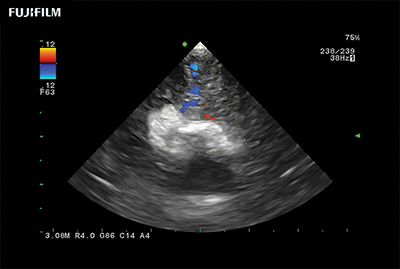

Advanced guidance for the most critical surgical decisions

Fujifilm continues to listen to the experts, our neurosurgeons, by designing an ultrasound system specifically tailored for the Operating Room.

Guidance is the fundamental purpose for all of our surgical ultrasound technology. Fujifilm is committed to designing tools that help neurosurgeons navigate inside the human body and provide the necessary information to immediately make critical surgical decisions.

With the ARIETTA Precision the new vision for surgical ultrasound is here.